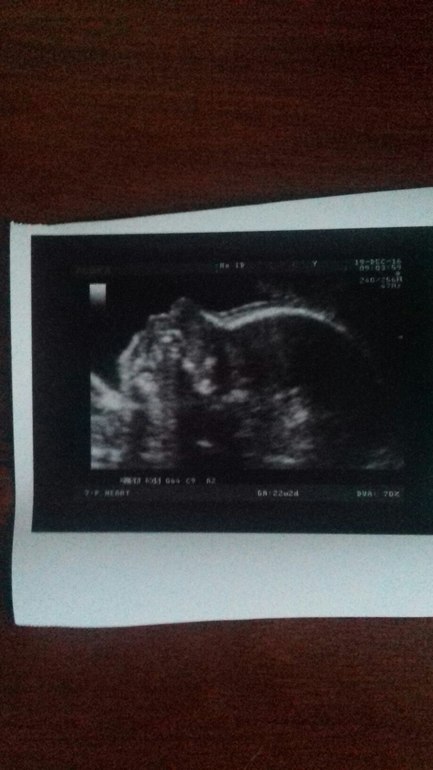

Девчата, всем привет! Мы растём, сегодня нам 22недельки и 2 дня) Пошла я сегодня на узи. Как и было в 20 недель узист подтвердил -пароксизмальную синусовую брадикардию....

Я опять в расстройствах. Хотя он меня успокоил ,что страшного в этом ничего нет... И на малыше никак не скажется. Роды обычные, никакого кесарева не надо. В целом здоровый малыш. И всё таки в нашей семье будет ещё одна принцесса.... Как же я рада....

. Вся расплылась в улыбке)))) Сделали очередную фоточку...такая она принцесска маленькая...

хорошенькая...